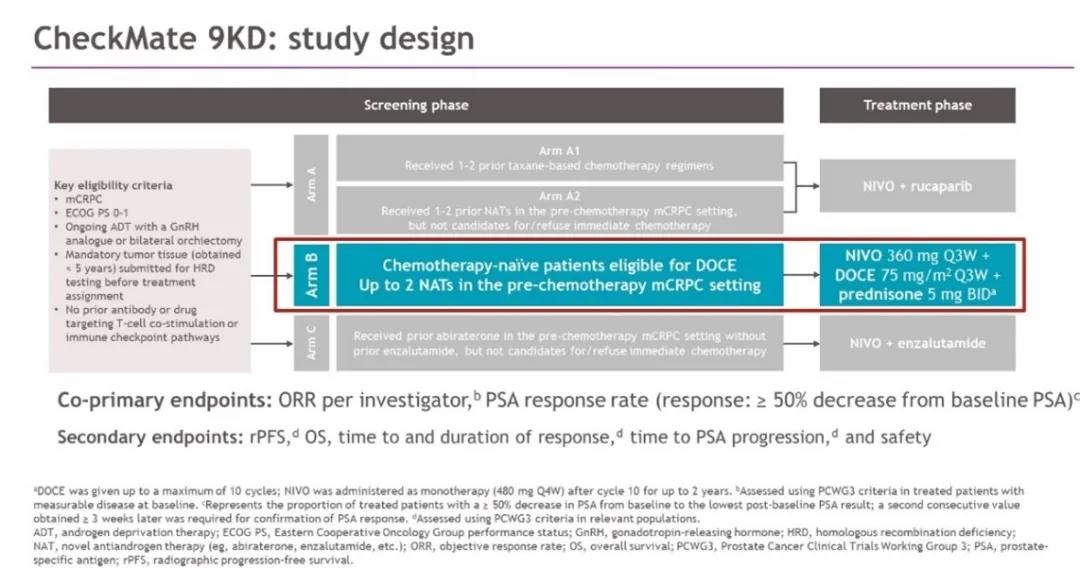

CheckMate 9KD(NCT03338790)研究是一项纳武利尤单抗联合方案治疗mCRPC的2期临床研究。研究根据患者的既往治疗状态将患者分为A、B、C三个...